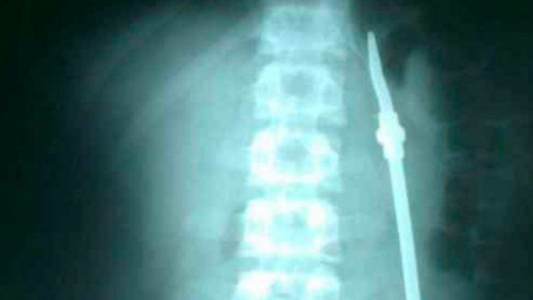

Tiene 16 años y era buscado por robar un teléfono celular y balear dos veces en el tobillo a la víctima